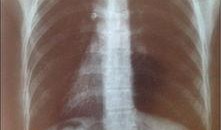

最近在网上看到一个超级劲爆的消息,就是2024年的胸片爆料啦!没错,就是那种能让你瞬间了解最新潮流趋势的胸片。今天,我就要带你全...